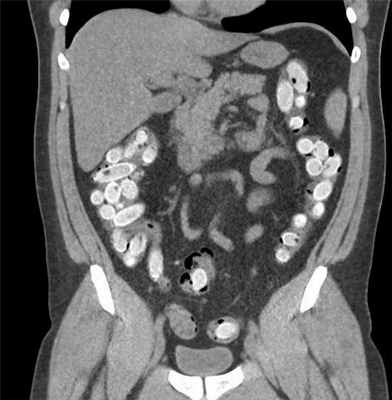

Мужчина пытался провезти в себе наркотики. В желудке и прямой кишке были обнаружены 73 упаковки наркотических средств, 2020 г